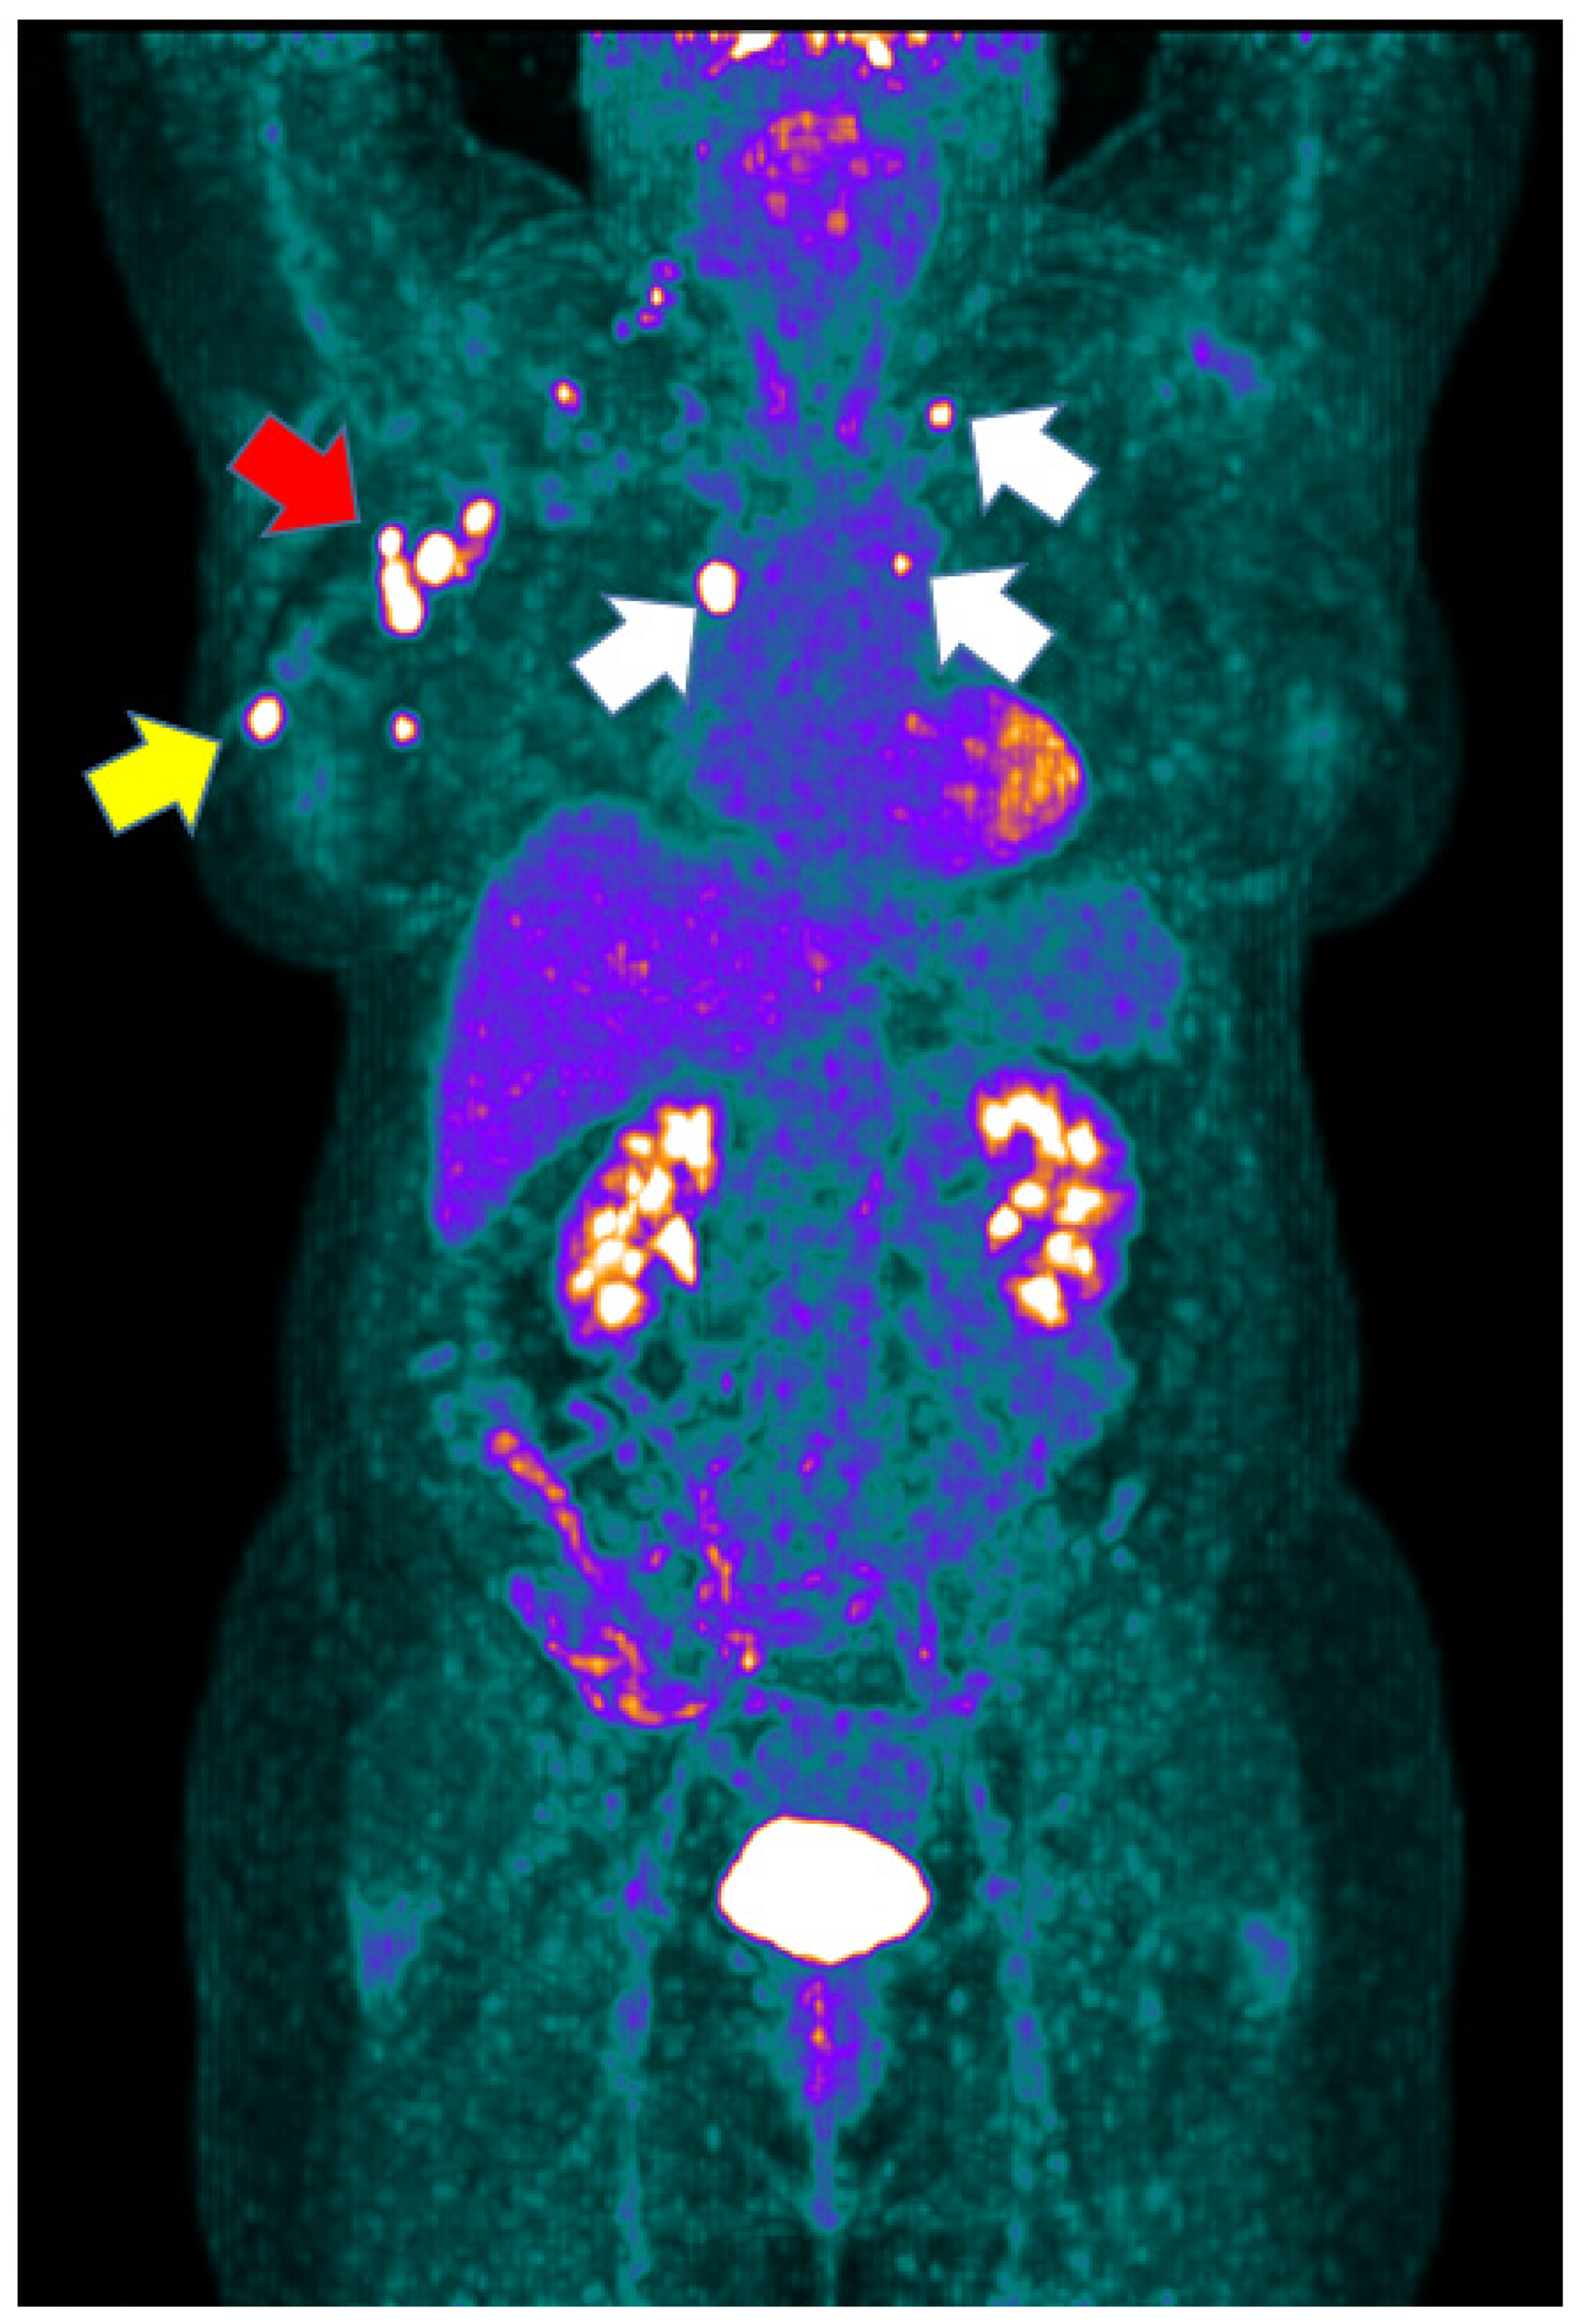

3.1. [18F]FDG PET/CT Results

3.2. [18F]FDG PET/CT Semiquantitative Data and Response to NAC

3.3. [18F]FDG PET/CT Semiquantitative Data and Survival